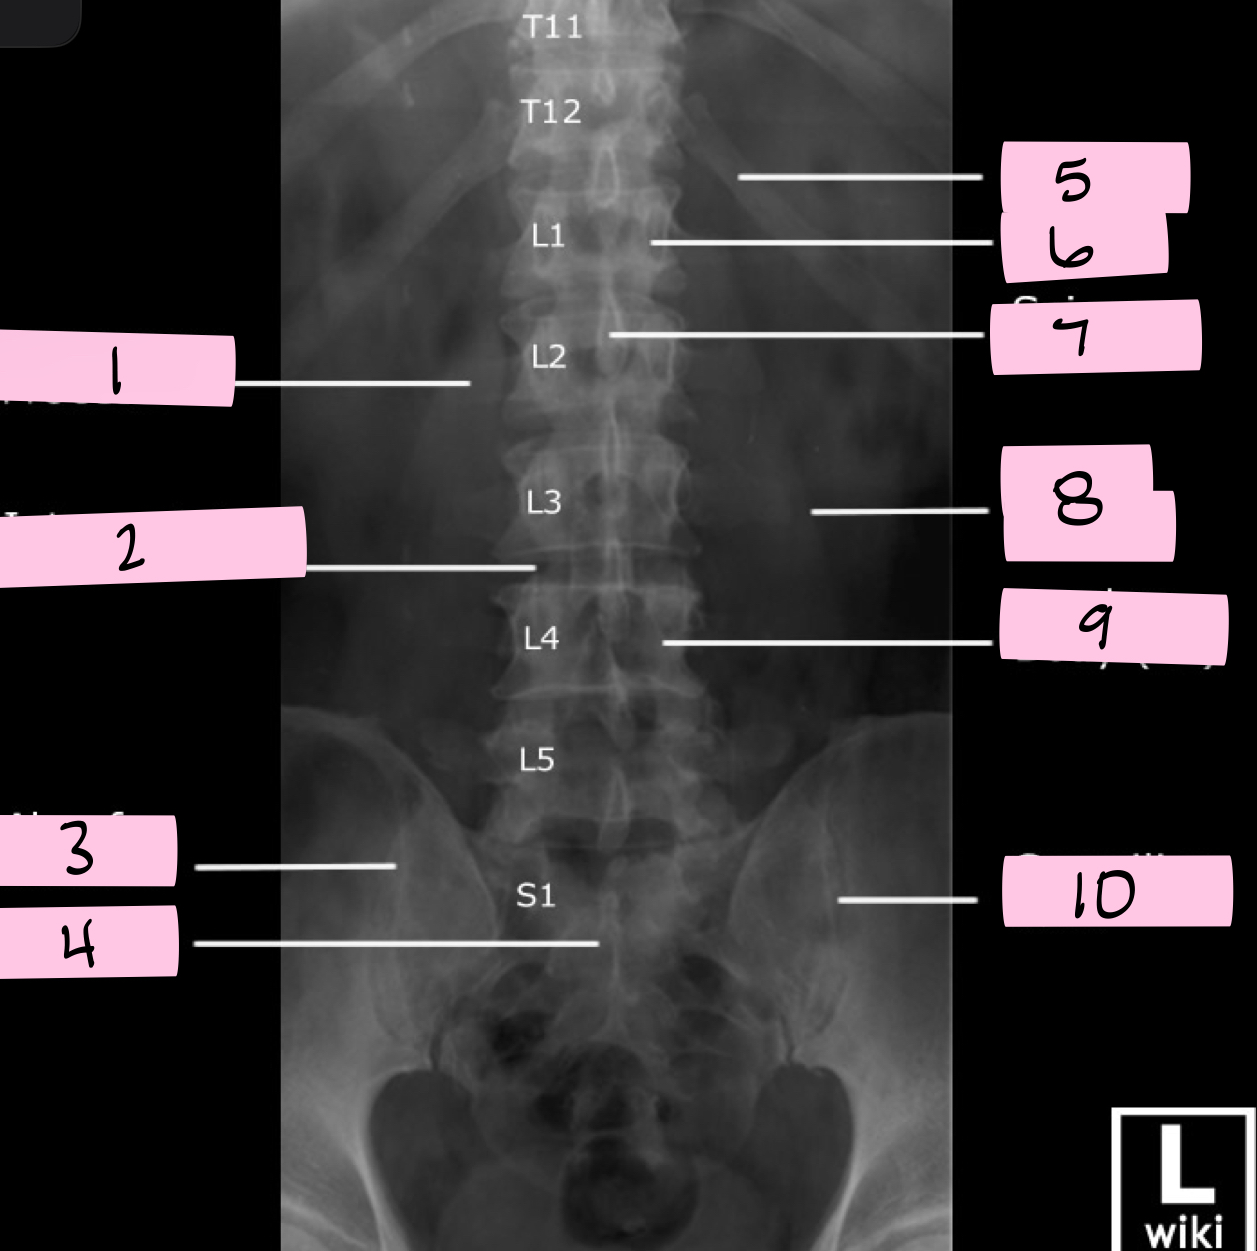

What is 1 pointing to?

Superior articular process

What is 2 pointing to?

Zygapophyseal joint

What is 3 pointing to?

Transverse process

What is 4 pointing to?

Pars interarticularis

What is 5 pointing to?

Inferior articular process

What is 6 pointing to?

Pedicle

What is 7 pointing to?

Scotty dog